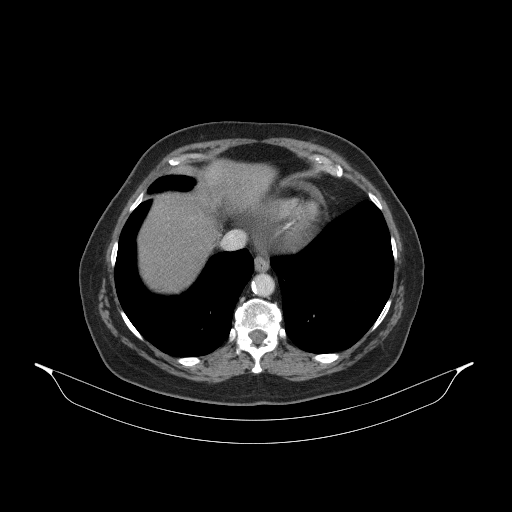

Image Grid

4Γ—3 grid: Rows show different image types (Original NATIVE, Reconstructed NATIVE, Original VENOUS, Generated VENOUS), Columns show windowing techniques (No Window, Lung Window, Mediastinum Window)

Mediastinum window (WL 40, WW 400 β†’ Low βˆ’160, High +240)